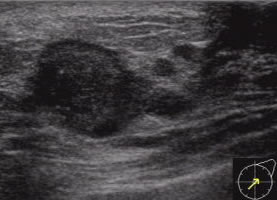

エコー検査ともいいます。マンモグラフィや視触診と組み合わせて行なわれることが多いです。超音波(人間には聞こえない音)を体に向かって当てて、臓器からの音の反射を画像にして観察する検査です。

痛みを伴わない、しこりは大きくても小さくてもよく検出される、乳腺が発達している若い人にも適している、といった長所があります。

しかし、石灰化はわからないので、マンモグラフィと組み合わせての利用が推奨されます。